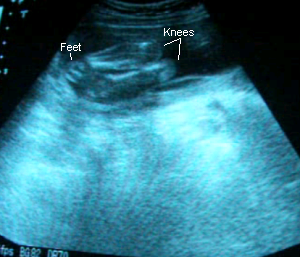

31 Weeks 1 Day

November 28, 2006: Blood pressure and urinalysis were great. Alaethia’s still in the head-down position. I’ve been feeling her little feet in my ribs and tugs around my belly, which the doctor says might be her pulling on the umbilical cord. She’s measuring at 30w3days according to her size although I’m 31 weeks 1 day, which Dr. C. says is fine but it makes me anxious since it might mean she’ll be here later than sooner :P. Although, I would like her to wait till 38 weeks at least! Dr. C. says she’s growing perfectly and confirmed for the 4th time that she’s a girl. From this sono, it looks like she’ll have Eenan’s round face and Jaylen’s lips…and probably my nose. I can’t wait to meet her!

Sono pic:

Her leg.